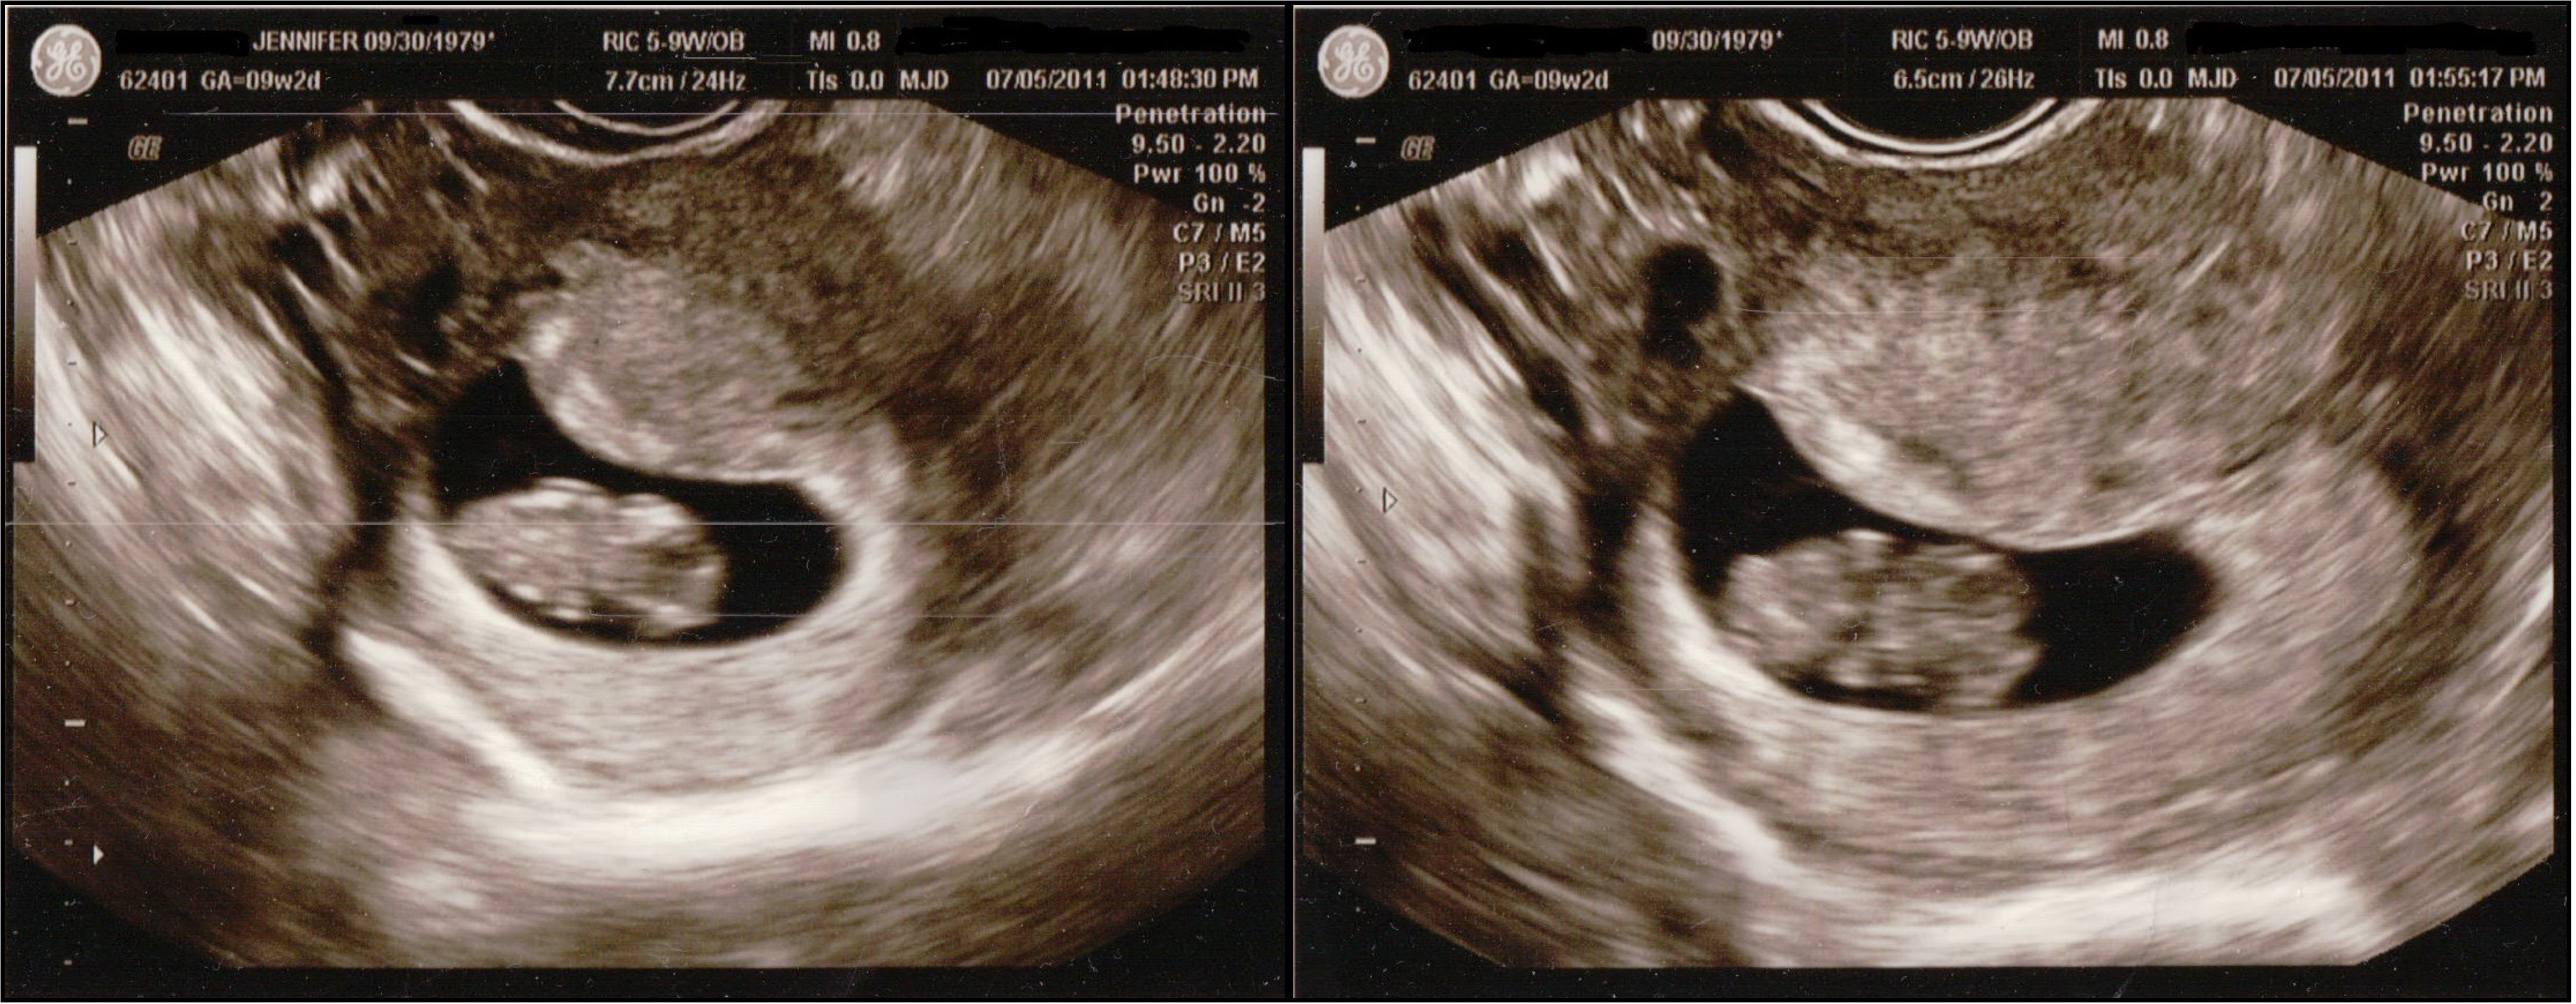

Early Ultrasound 9 weeks 2 days

Yesterday I had another early ultrasound. This was the follow-up to the one I had two weeks ago. The baby was very small at the time so they wanted to make sure a twin wasn’t hiding in there.

Apparently there wasn’t. There’s just one sweet little baby in there. She had no trouble finding the baby this time. We saw the heartbeat and it was 167. We also got to see the little one give us a few wiggles and shimmies 🙂

(Click on photos to enlarge them.)

The head is to the right and you can see the baby’s arm buds!